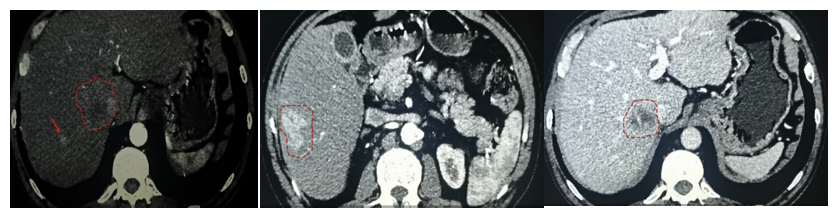

但至第1次TACE术后约15个月时间(2021年6月15日),复查发现肝内肿瘤明显进展(图5);AFP明显升高:6231.00 ng/mL。此时更换方案为二线靶向药物瑞戈非尼,160mg,qd,3周方案。同时联合免疫治疗:卡瑞利珠单抗200mg,静脉点滴,每3周1次。

图5.2021年6月15日上腹部CE-MRI

更换方案后1个月(2021年7月20日),肝内肿瘤病灶仍持续进展(图6),AFP升高至10795.00ng/mL。

图6.2021年7月20日上腹部CE-MRI

术后17个月左右(2021年8月27日),上腹部CE-MRI:肝内肿瘤病灶明显消退(图7)。AFP降至92.89ng/mL。

图7.2021年8月27日上腹部CE-MRI